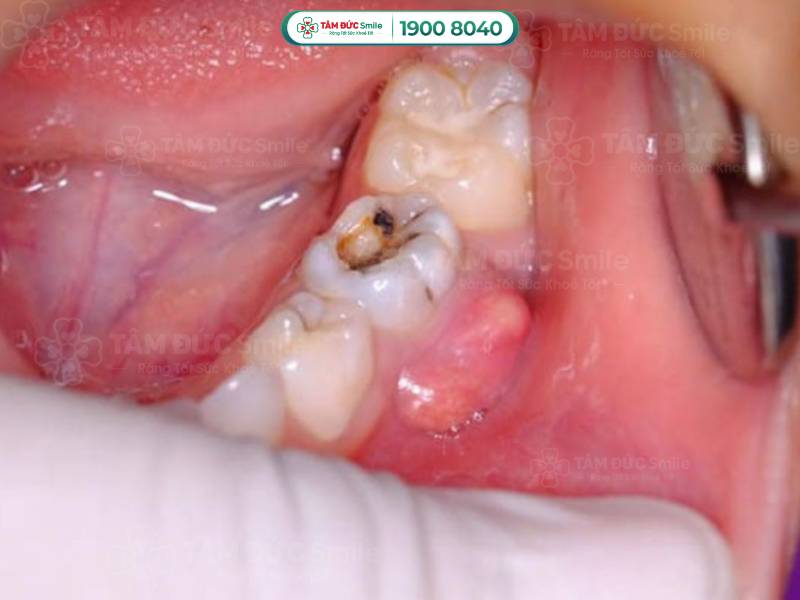

Viêm ổ răng có mủ là tình trạng viêm ở chân răng hoặc lợi tạo thành ổ viêm ở cuống răng. Một số nguyên nhân chính dẫn đến viêm ổ răng có mủ bao gồm:

- Sâu răng: Sâu răng làm hỏng men răng và ngà răng, vi khuẩn thông qua lỗ sâu tiếp cận tủy răng, gây viêm và nhiễm trùng.

Viêm ổ răng có mủ là tình trạng viêm ở chân răng hoặc lợi